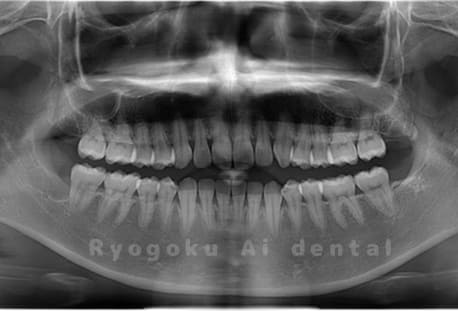

Case03

- 原因

- 上顎、下顎の親知らず

- 治療内容

- 上下4本の親知らずを抜歯したケースです。

<リスク・副作用>

手術後は痛み、腫れ、痺れなどの副作用が生じる場合があります。